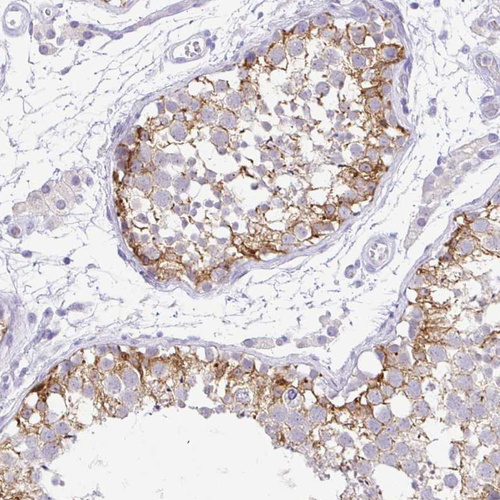

Immunohistochemistry analysis in human testis and skin tissues using HPA034604 antibody. Corresponding FATE1 RNA-seq data are presented for the same tissues.